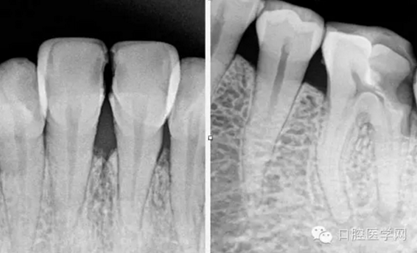

術(shù)前片(治療前知道齲壞的程度,根管的走向)

》工作長度的確定。

特殊情況可以插針拍片確定工作長度(一般我比較相信根測)